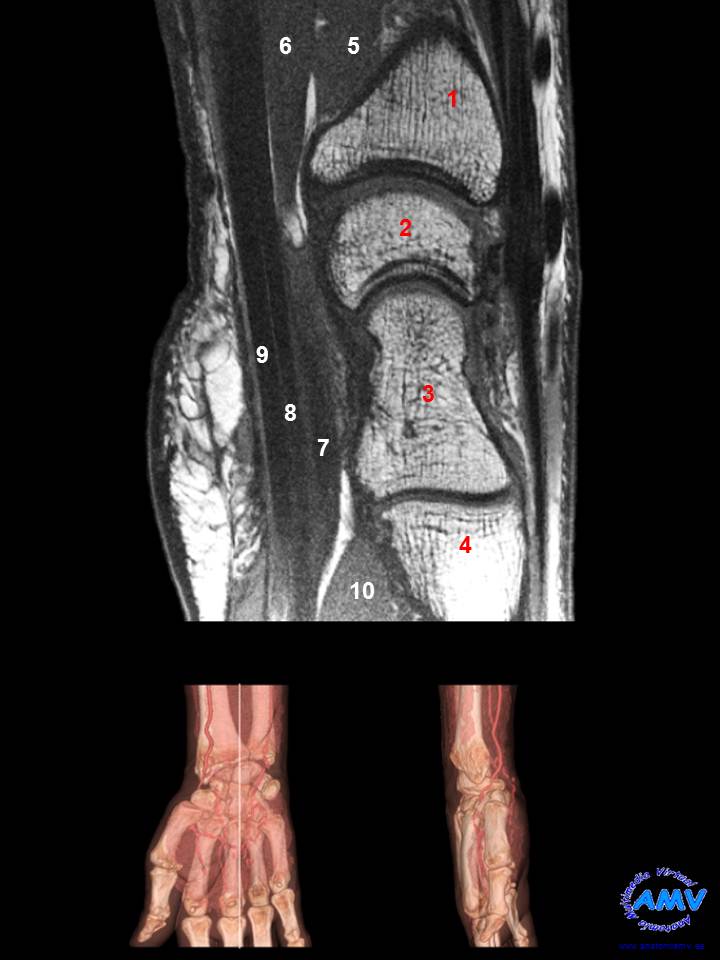

RMN Sagital de Muñeca

ms_rmn_11.jpgIndique que estructura se señala con el número correspondiente:

El nº 1 señala al hueso .

El nº 2 señala al hueso .

El nº 3 señala al hueso .

El nº 4 señala a la base del .

El nº 5 señala al músculo .

El nº 6 señala al músculo .

El nº 7 señala al tendón del músculo .

El nº 8 señala al tendón del músculo .

El nº 9 señala al tendón del músculo .

El nº 10 señala a la cabeza oblicua del músculo .